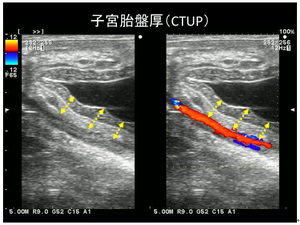

① 超音波検査(経直腸、経腹壁[F3.1]):超音波検査で主に見たいものはCTUP(子宮胎盤厚)や胎動、胎子心拍、羊水/尿膜水の性状変化となります。特にCTUPについては経直腸の超音波検査で観察、測定がし易く、重要なポイントとなります(写真2)。正常妊娠でも妊娠月齢とともにCTUP値は増加しますが、目安として、270–300日で8 mm以上、300–330日で10 mm以上、330日以降で12 mm以上の場合には胎盤炎によるCTUPの異常な肥厚が考えられます。また厚さだけでなく、辺縁不整や浮腫像を認める場合も胎盤炎を疑います(Kimura, 2018)。また、妊娠期が進むにつれて胎児も大きく重くなり母馬のお腹に沈んでいくため、胎児心拍や羊水/尿膜水の正常変化については5か月齢ころから経直腸ではなく経腹壁からアプローチする必要が出てきます。

今回の症例では、経過観察中に経直腸超音波検査にてCTUP部位に一部浮腫像認めておりました。血中ホルモン検査では各の定期検査結果を見直したところ、症状がでる1か月前に異常なプロゲステロン上昇動態を認めておりました。また、炎症マーカーであるSAAについては、日本の生産地でまだ活用されていない印象で、私自身もあまり馴染みがありませんでしたが、今回の症例サンプルなども用いて今後検証したいところです。[F4.1]